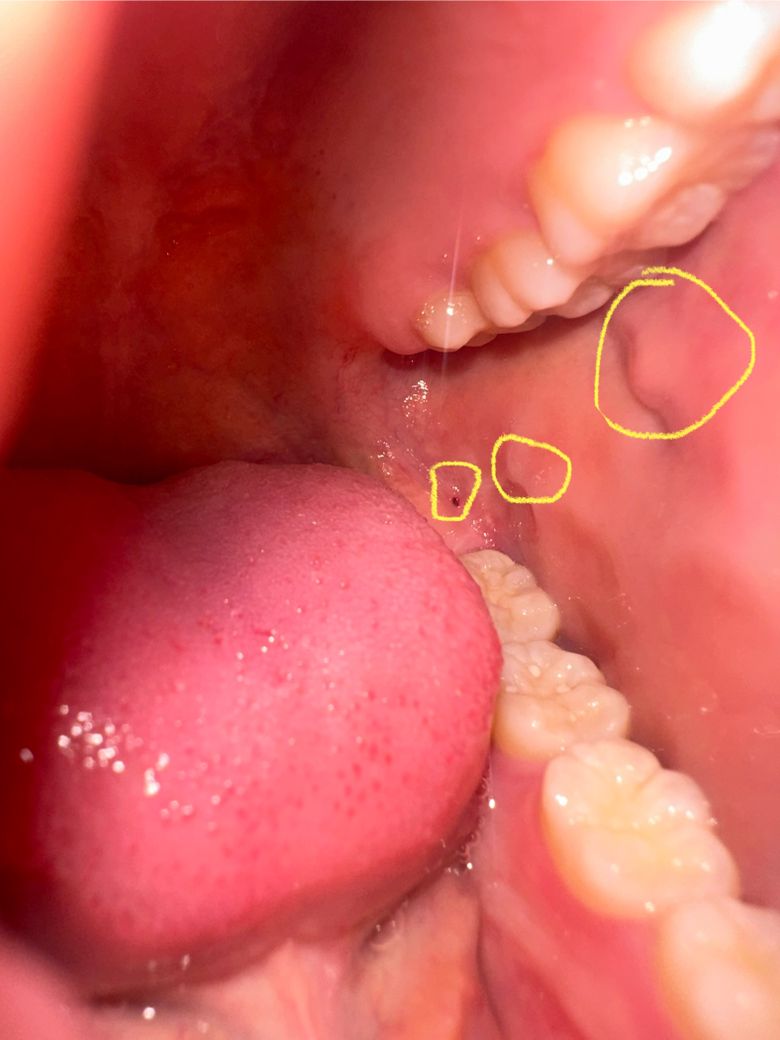

사진에 노란색 동그라미 친 부위에 볼 안쪽 살이 두 개 돌기처럼 튀어나와 있고, 어금니 뒷쪽에 피 고였을 때 생기는 것처럼 보이는 점이 있습니다 둘 다 통증은 따로 없어요 오늘 발견해서 정확히 언제부터 있었는지는 모르겠습니다 혹시 원인이 무엇일까요? 구강암일 확률은 얼마나 되나요?

가장 큰 동그라미는 stensen duct로 귀밑샘의 침 분비구이고 중간 동그라미는위아래 어금니가 볼을 씹거나 압력을 가해서 생기는 것입니다. 그리고 마지막 빨간 점도 위쪽 사랑니가 해당 부분을 자극해서 생긴 것으로 셋 모두 전혀 문제 없으므로 걱정하지 않으셔도 되겠습니다.